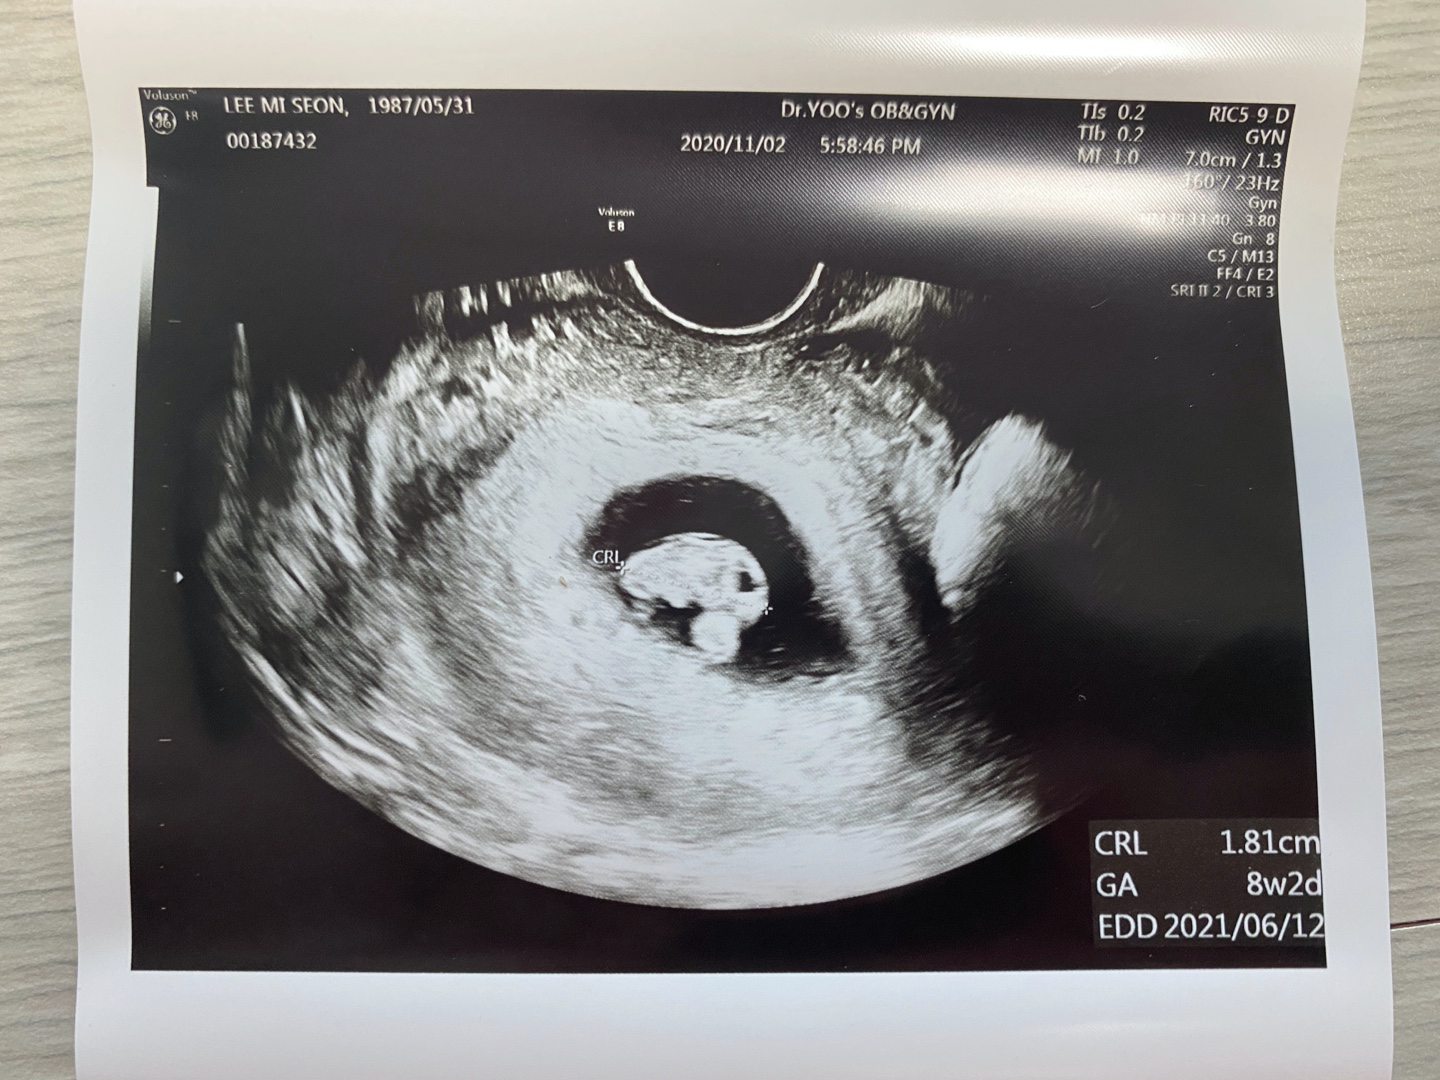

이제 배아 단계에서 태아라고 불러도 단계라고 한다. 아직 2cm도 안되는 쪼꼬미가 태아라니ㅎㅎ

고새 더 컸다고ㅋㅋ 심장도 잘 뛰고 있고 크기도 좋다고 앞으로 2주에 한번씩 와도 좋다고 하셨다고 했다.😁

꼬리가 없어지고 팔, 다리가 살짝 구분되며 보이기 시작한다고 했는데 초음파사진만 놓고 봐서는 아직도 잘 보이지 않고 그런다.